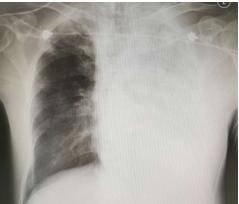

原本還有力氣哭鬧要回家的女童,經過安撫後漸漸安靜下來,才過沒多久,父母便發現女童呼吸狀況變得詭異、越來越喘,醫師當下急照X光檢查,震驚發現女童「肺部已經白掉大半了」,嘴角甚至流出粉紅色泡泡狀的口水,這是病毒已經影響女童腦幹的跡象,情況十分危急。